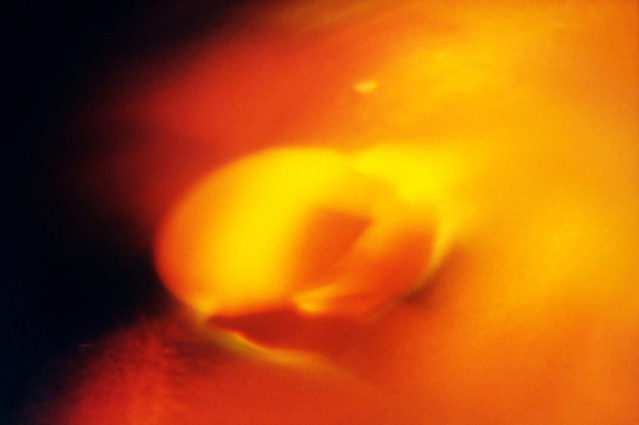

Исследователи сравнили эффективность переноса свежих и криоконсервированных эмбрионов у женщин без поликистоза яичников

В новом исследовании вьетнамские и австралийские ученые из университета медицины и фармации в Хошимине и Южно-Австралийского института здравоохранения и медицинских исследований в Аделаиде сравнили эффективность переноса свежих и замороженных эмбрионов при ЭКО у женщин без синдрома поликистоза яичников.

Всего в работу было включено 782 женщины с бесплодием, которое не было связано с синдромом поликистоза яичников. Все пациентки были поделены на 2 группы: в первой применялся перенос криоконсервированных эмбрионов (n=391), а во второй — свежих (n=391). Основной конечной точкой эффективности методов являлось развитие беременности после первой процедуры переноса эмбрионов.

После первого завершенного цикла беременность была зафиксирована у 142 (36,3%) женщин из первой группы и 135 (34,5%) — из второй (отношение рисков (ОР) для первой группы — 1,05, 95% доверительный интервал [ДИ], 0,87 до 1,27, P = 0,65). Частота рождаемости составляла 33,8% и 31,5% соответственно (ОР — 1,07, 95% ДИ, 0,88 до 1,31).

Результаты работы показали, что перенос замороженных эмбрионов не связан с увеличением частоты развития беременности и рождаемости в сравнении с методом свежих эмбрионов у женщин без поликистоза яичников.